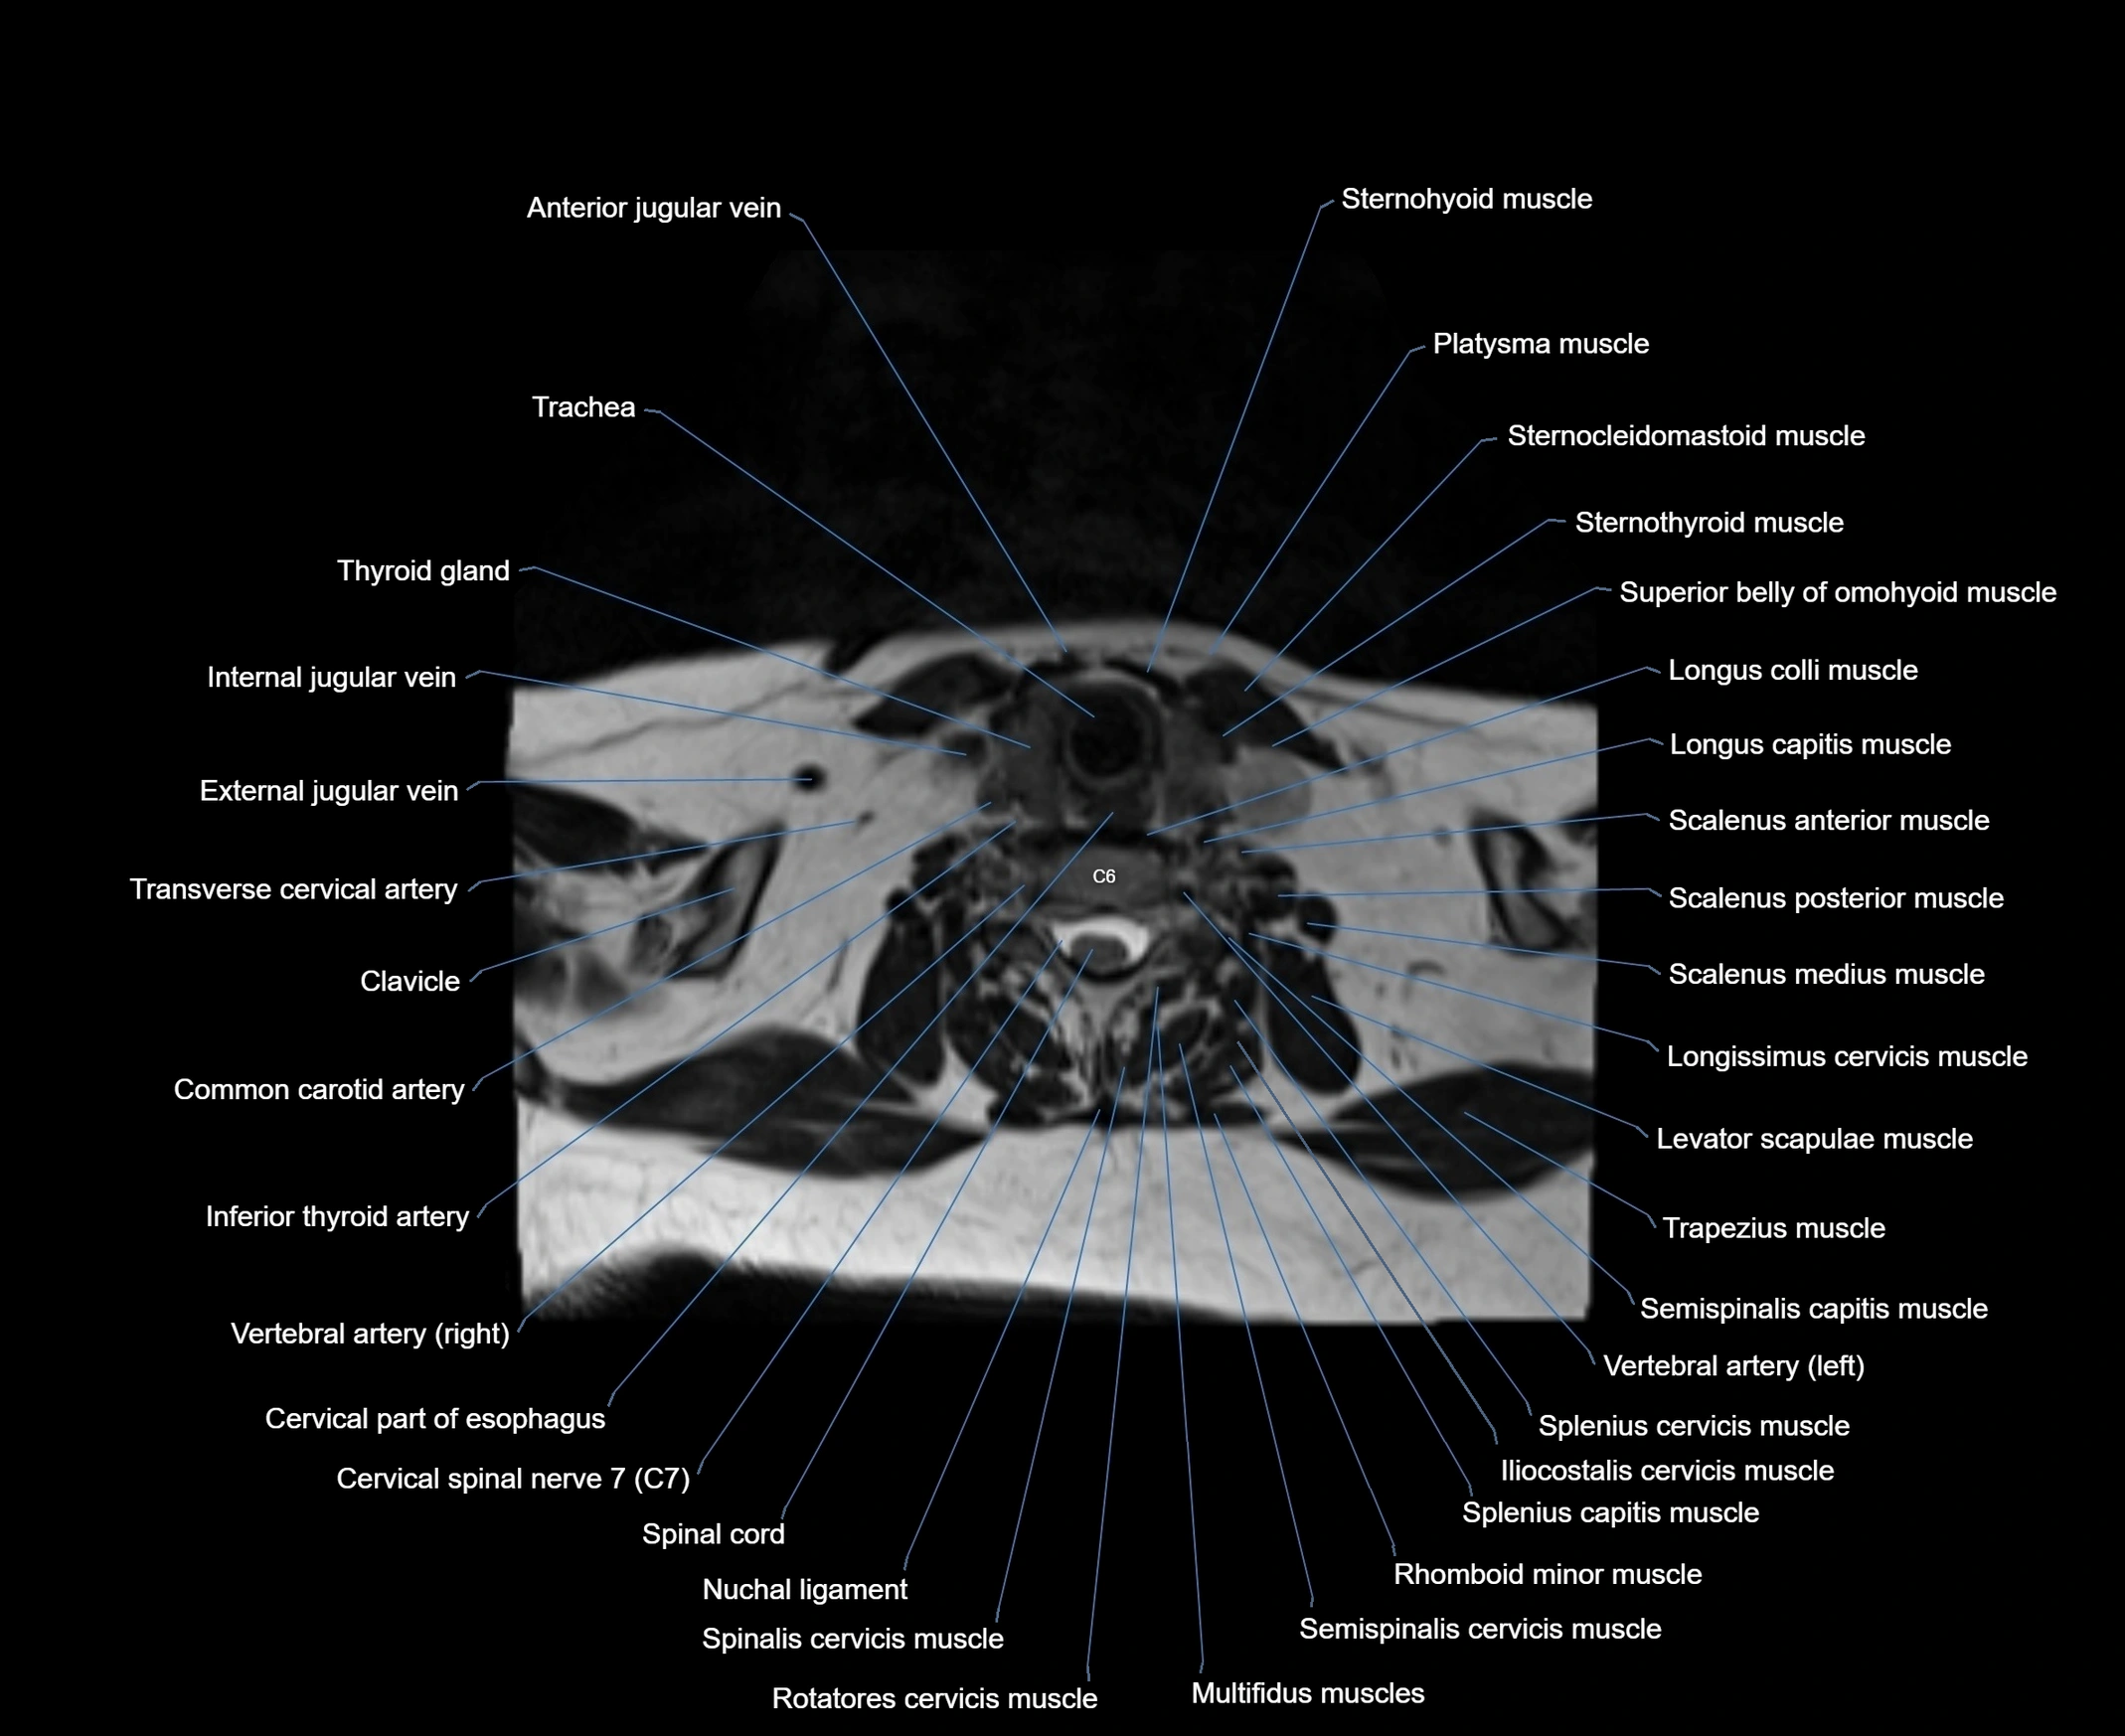

- Anterior jugular vein

- Cervical part of esophagus

- Cervical spinal nerve 7 (C7)

- Clavicle

- Common carotid artery

- External jugular vein

- Iliocostalis cervicis muscle

- Inferior belly of omohyoid muscle

- Inferior thyroid artery

- Longissimus cervicis muscle

- Longus capitis muscle

- Longus colli muscle

- Multifidus muscles

- Nuchal ligament

- Platysma muscle

- Rotatores cervicis muscle

- Rotatores cervicis muscles

- Scalenus anterior muscle (Anterior scalene muscle)

- Scalenus medius muscle (middle scalene muscle)

- Scalenus posterior muscle (Posterior scalene muscle)

- Semispinalis capitis muscle

- Semispinalis cervicis muscle

- Spinal cord

- Spinalis cervicis muscle

- Spinous process of vertebra

- Splenius capitis muscle

- Splenius cervicis muscle

- Sternocleidomastoid muscle

- Sternohyoid muscle

- Sternothyroid muscle

- Superior belly of omohyoid muscle

- Thyroid gland

- Trachea

- Transverse cervical artery

- Trapezius muscle